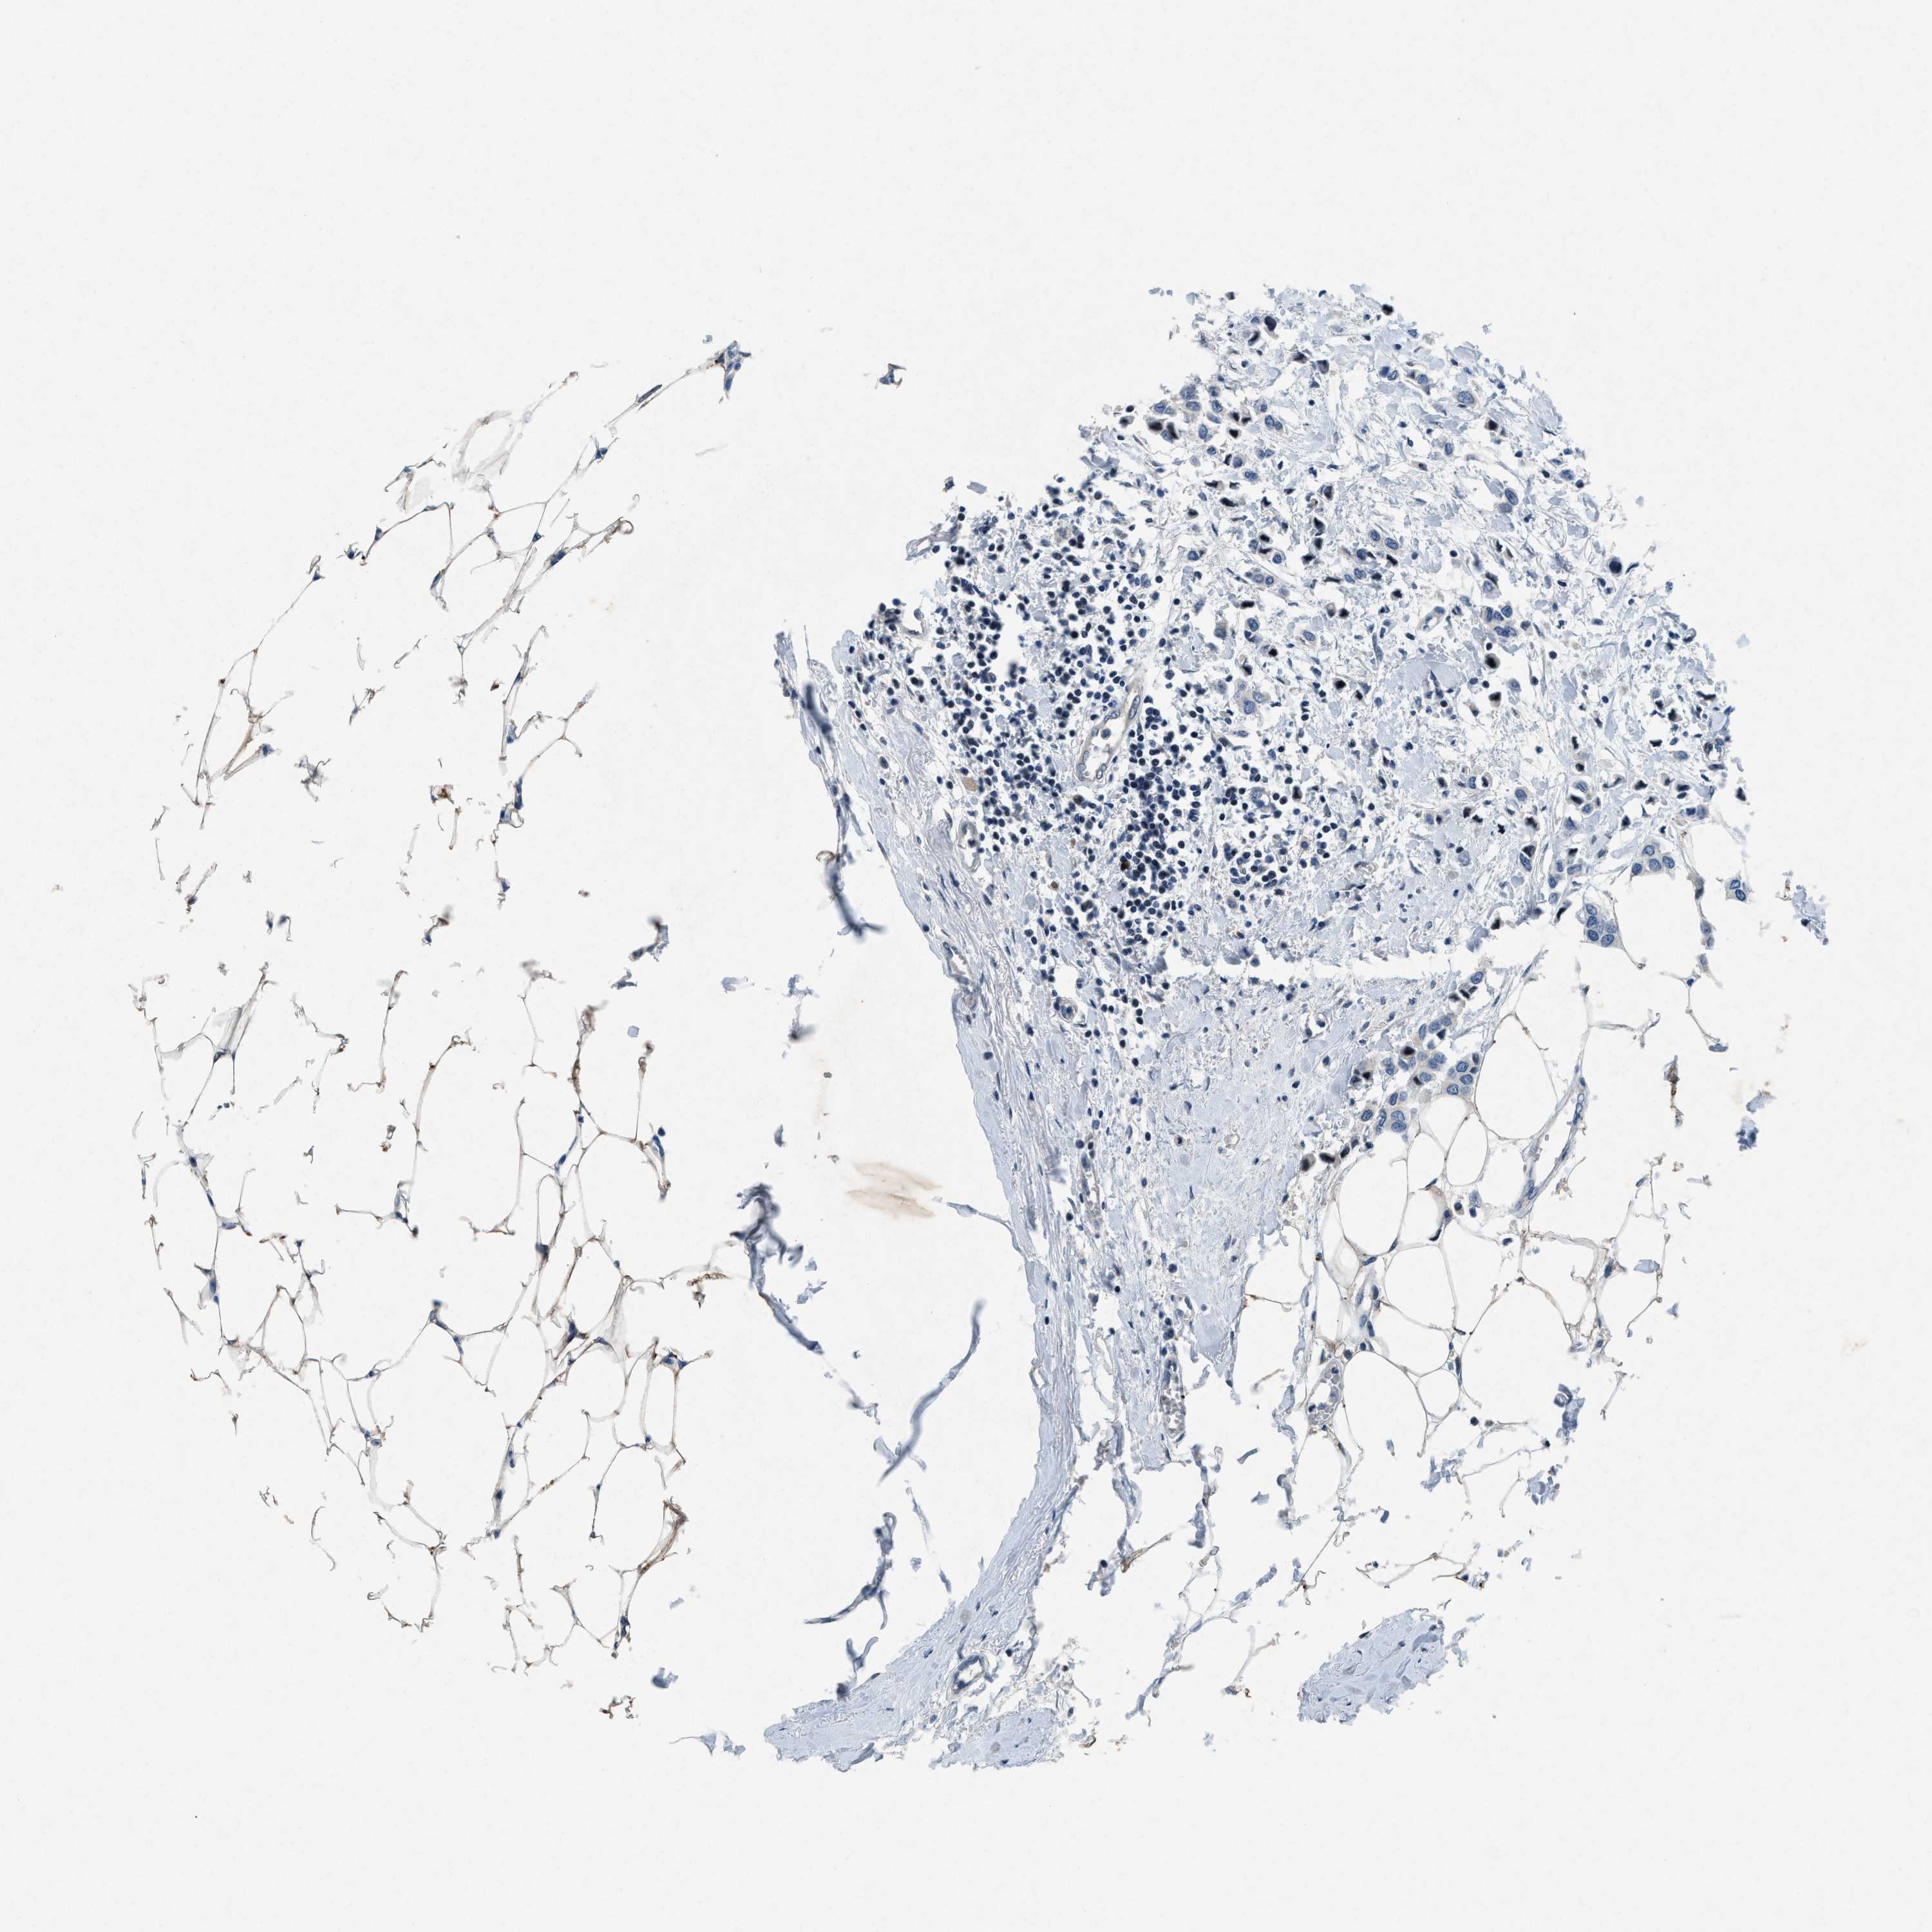

CANCER BREAST CANCER Show tissue menu

BRCA TCGA BRCA VALIDATION PROTEIN EXPRESSION